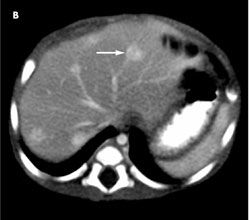

A complete blood cell count with differential, and electrolyte and liver enzyme levels are normal. CT scans of the abdomen without (A) and with (B) contrast show multiple solid hypoattenuated lesions in both lobes; the largest lesion (arrow), of 11 mm, in hepatic segment VI significantly enhances with intravenous contrast.